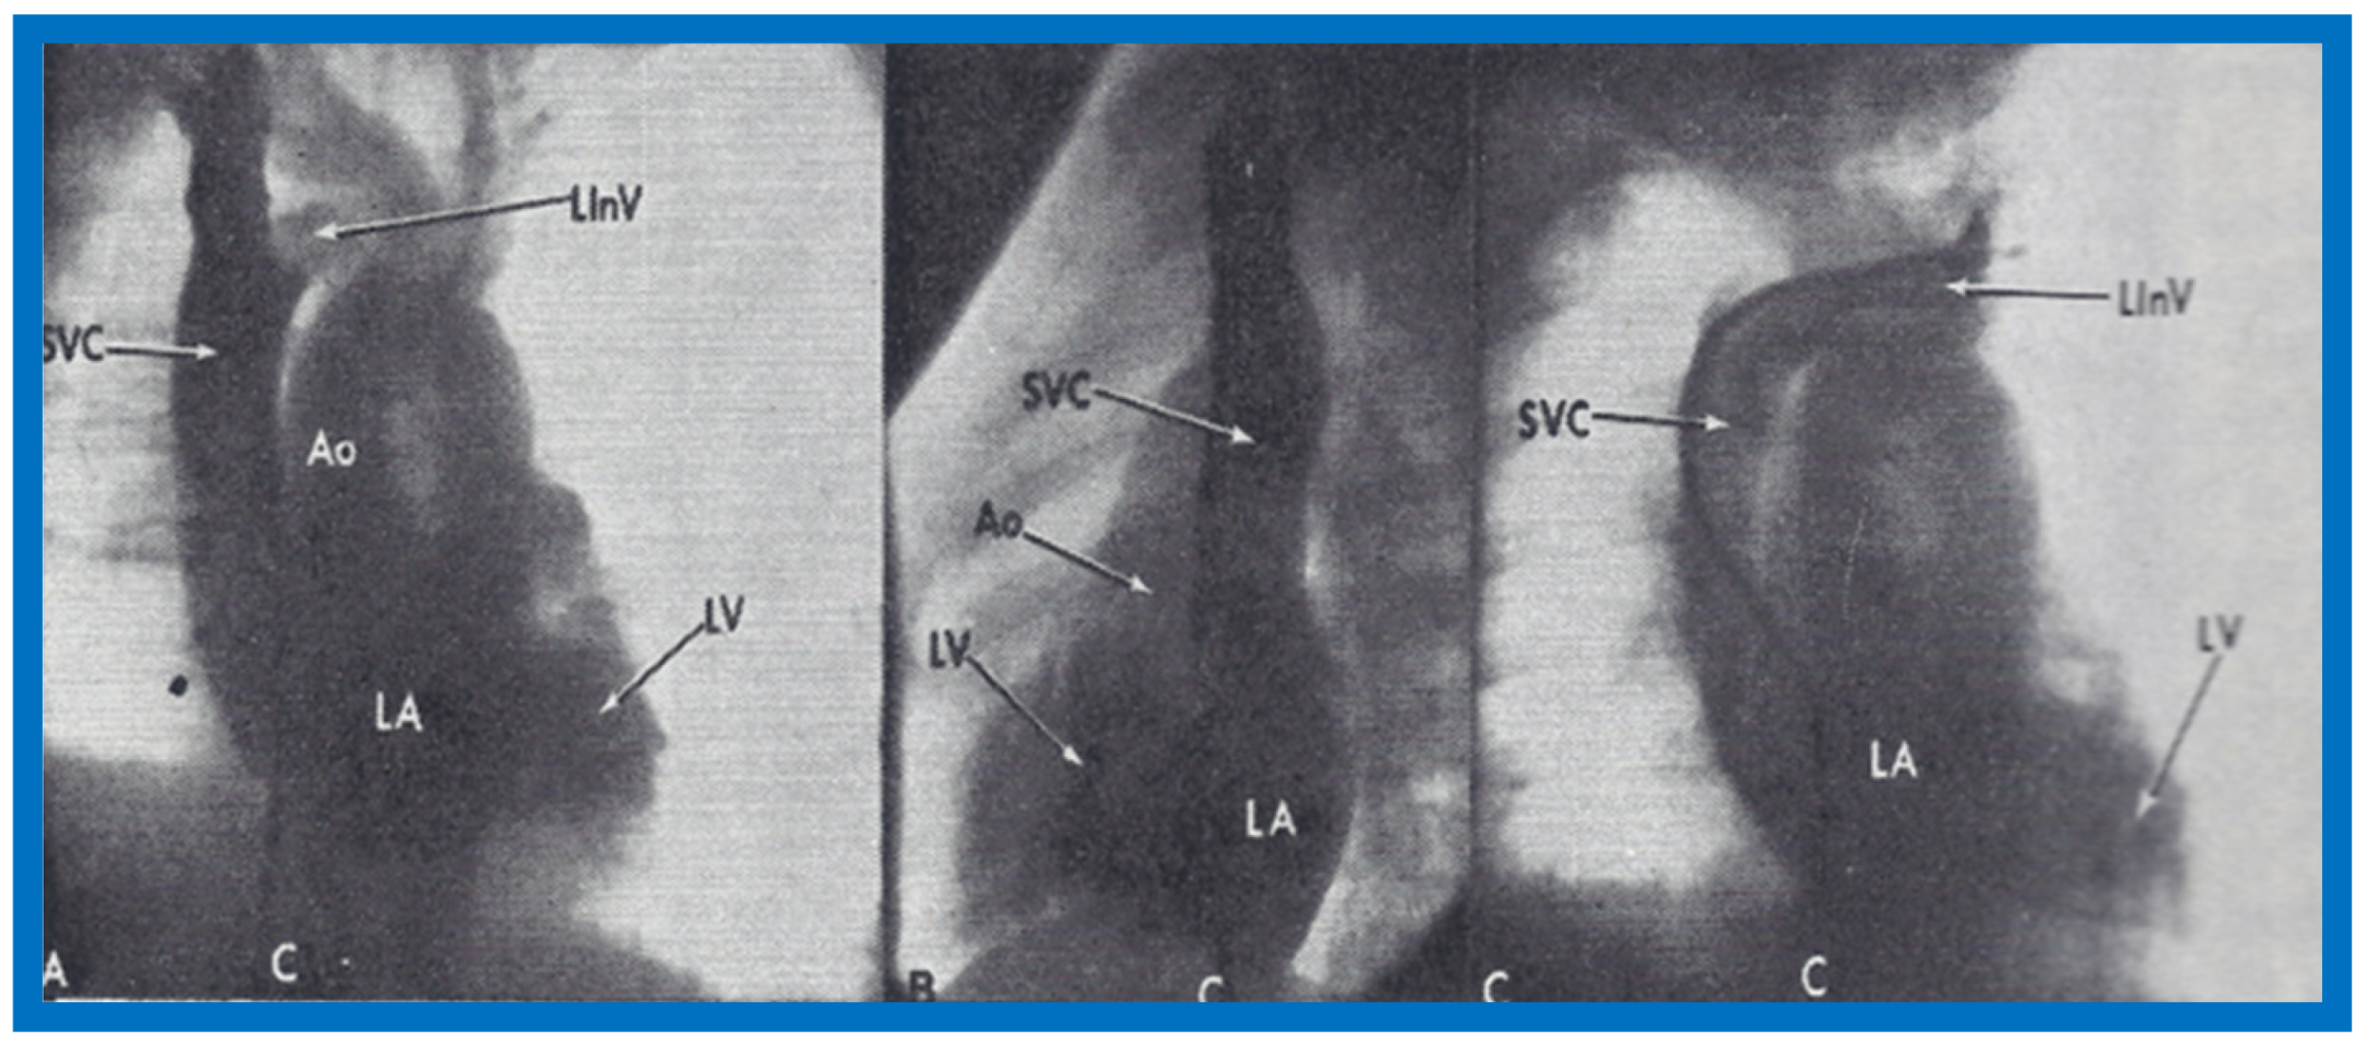

At the age of 8 months, cardiac catheterization with selective cineangiography was performed. The left atrium (LA) was catheterized via a tight patent foramen ovale, and the catheter was advanced from the LA into the superior vena cava (SVC) and into both right and left innominate veins. The right heart saturations were low (60–62%) without any evidence for a step up. The pulmonary venous saturations were normal (98%) with a step down in the left atrium and left ventricle (79%). The pressures in all cardiac chambers were normal (See Table 1 of [2]). Selective cineangiography into the right (Figure 6A,B) and left (Figure 6C) innominate veins confirmed the diagnosis of anomalous connection of the right SVC to the LA. No persistent left SVC was identified. Because of a lack of other symptoms and only mild polycythemia (hemoglobin of 15 gm%), surgical correction was deferred at that time with a plan for surgery at a later date.

Figure 6.

Angiographic frames from injections into the right innominate (A,B) and left innominate (LInV) (C) veins demonstrating direct opacification of the right superior vena cava (SVC), left atrium (LA), left ventricle (LV) and aorta (Ao) without opacification of the right heart structures. C, Catheter. Reproduced from Truman T.A., Rao P.S., Kulungara R.J. [2].

An extensive review of the literature revealed only four published cases of anomalous connection of the right SVC to the LA as of the time of our review [2]. Ages at diagnosis were 2 to 34 years, with our subject being 8 months-old. All of them presented with cyanosis and diagnosis was made by angiography, except for our case, which was initially diagnosed by contrast echocardiography and later confirmed by angiography. The differential diagnosis of cyanosis (and arterial desaturation) without any other abnormal cardiac findings includes pulmonary arteriovenous fistula, connection of pulmonary artery to the LA and of course anomalous systemic venous connection to the left atrium. In pulmonary arteriovenous fistula and connection of pulmonary artery to the LA, the contrast would first appear in the right ventricle before the LA, LV and Ao. In addition, differential contrast patterns at the site of injection into the veins of the upper and lower extremities should not be present with pulmonary artriovenous fistula and connection of pulmonary artery to the LA. The associated discussion also included a review of the possible embryological origin of anomalous systemic venous connection to the left atrium [2].